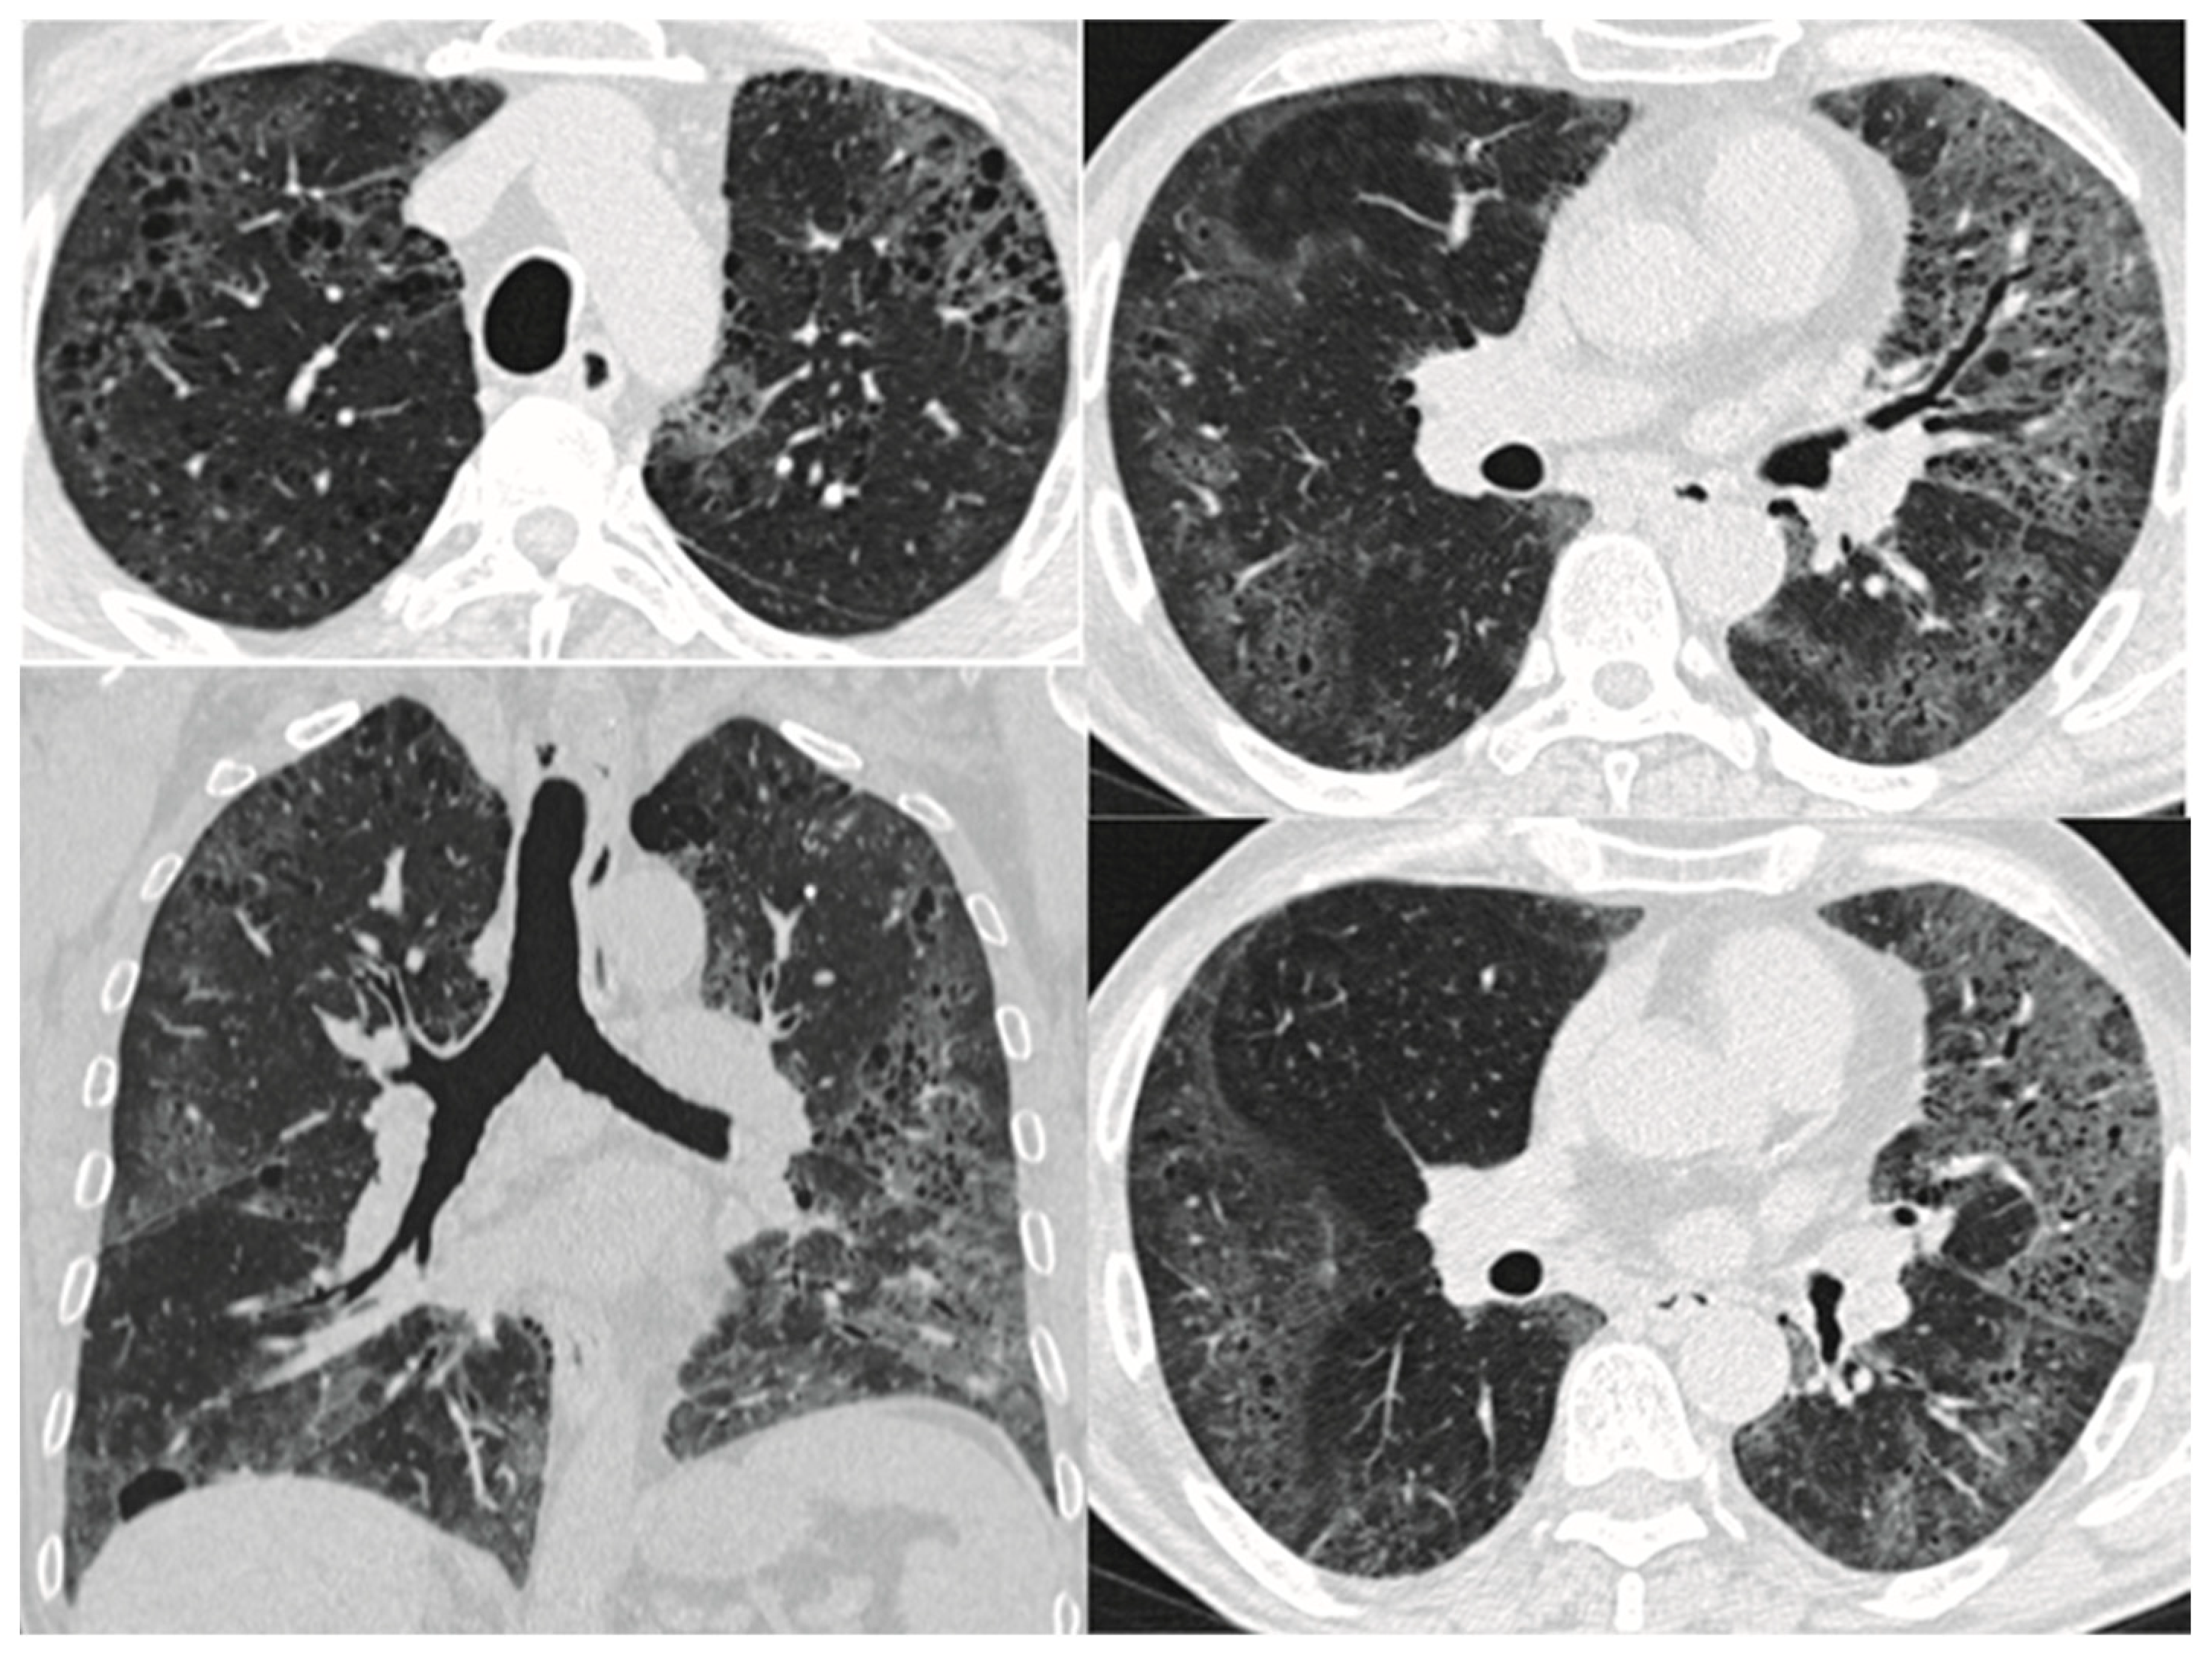

7. Lung Function

| Pathology | Small airways remodeling, fibrosis, and destruction of the lung parenchyma with an upper lobe predominance | Emphysema in the upper lobes and patchy fibrosis, fibroblast foci, and honeycombing—UIP/NSIP/DIP pattern—in the lower lobes. Presence of thick-walled cysts on a UIP background | Lung parenchyma and interstitium, with a lower lobe predilection |

| Imaging | Centrilobular and/or bullous emphysema | Coexistence of paraseptal emphysema in the upper zones of the lungs and the UIP/NSIP/DIP in the lower zones, thick-walled cysts in the area of fibrosis | UIP pattern |